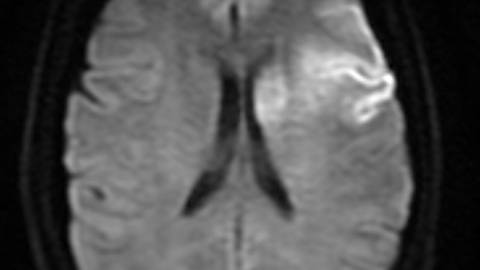

Figure 5. Diffusion-weighted sequence after thrombectomy.